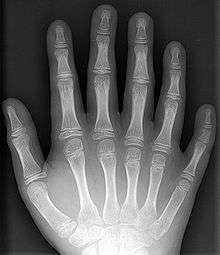

- Polydactyly – additional fingers or toes[6]

- Syndactyly – webbing between the fingers or toes[6]